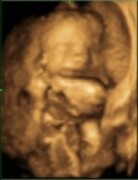

Ciao přátelé, tak screening máme za sebou. Na 60% to bude EMMA. Dle UZ vše oka - nosní kůstka přítomna, NT 1,52. Problém nastal u biochemie - volný beta hCG 125,9 a PAPP-A 4,457 s výsledkem "screening atypický". Žel ani má gyn ani na genetice mi neřekli co to znamená, respektive, jak moc jsou tyto h...

Konečně si můžu oddychnout!! I přes dnešní datum dopadl screening skvěle a navíc jsem dostala super fotečku miminka!!První to vypadalo,že spí, ale jakmile ho chtěla paní doktorka začít přeměřovat,tak začal s sebou mrskatPřítel byl se mnou a poprvé viděl toho pidi človíčka,kvůli kterému musí snášet t...

Tak mám screening také za sebou. Výsledky ještě nevím. jen podle UZV je vše v pořádku. Z krve výsledky nebyly,takže si budu muset asi pak zavolat ke své doktorce. Dnes jsem 13+1, ale mimi je prý mladší 12+3 a má jen 5,9 cm. Je to mrňousek. Nejvíc si pamatuji jeho hlavičku, páteř a prstíčky na ruce....

Ahoj holky, tak screening máme úspěšně za sebou..miminko je naprosto v pořáadku termín máme na 3.října- ikdyž to může být samozřejmě všechno jinak.Miminko k nám ale bylo stále zády, takže pan doktor nezjistil co by to mohlo být, jestli holčička nebo chlapeček...Jinak jsme 13+3 a měříme 7,11 cm to j...

Dneska jsem byla na prvním screeningu, bylo to kouzelný, byl u toho jak Martin tak Ondra. Koblížek má všechno jak má mít, všechny měřené hodny jsou v normě a stářím odpovídá 12+3 a já jsem 12+1 tak taky OK.

ahoj holky, tak hlásím, že dnes náš první screening dopadl na 1*, rizika máme úplně minimální. 13+0, mimi má 62 mm, poslouchali jsme i srdíčko a bylo to fakt super. Oproti minule se ale moc nehýbalo, tak si říkám, že asi spinkalo:-) Jsme nadšení. Jo a už víme i pohlaví,ale potvrdí se to až na příští...